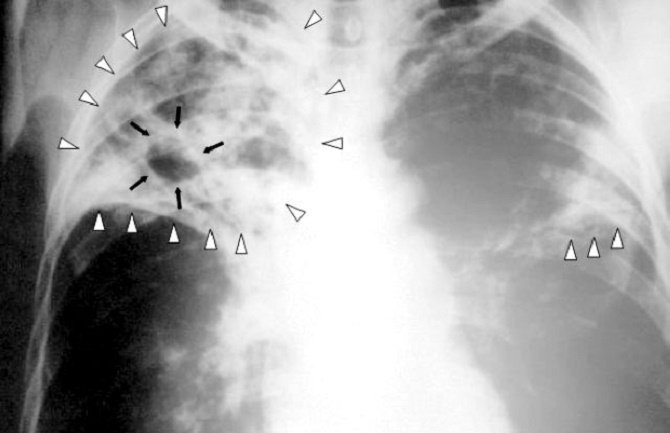

Procjenjuje se da se tuberkulozom u svijetu zarazi oko 8,6 miliona ljudi godišnje, a svake godine od tuberkuloze umre 1,3 miliona ljudi - smrtonosniji je jedino HIV.